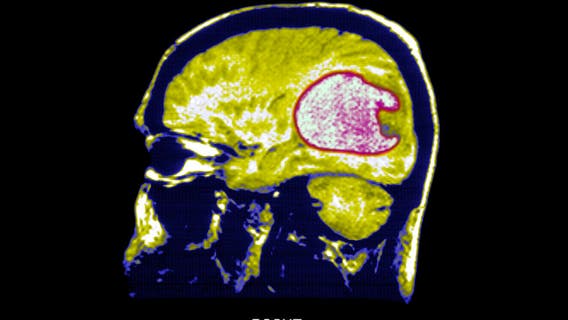

Scientists use new strategy to successfully shrink tumors in early brain cancer trials

Researchers converted immune cells from patients into "living drugs" with the ability to recognize and combat glioblastoma, a form of brain cancer.